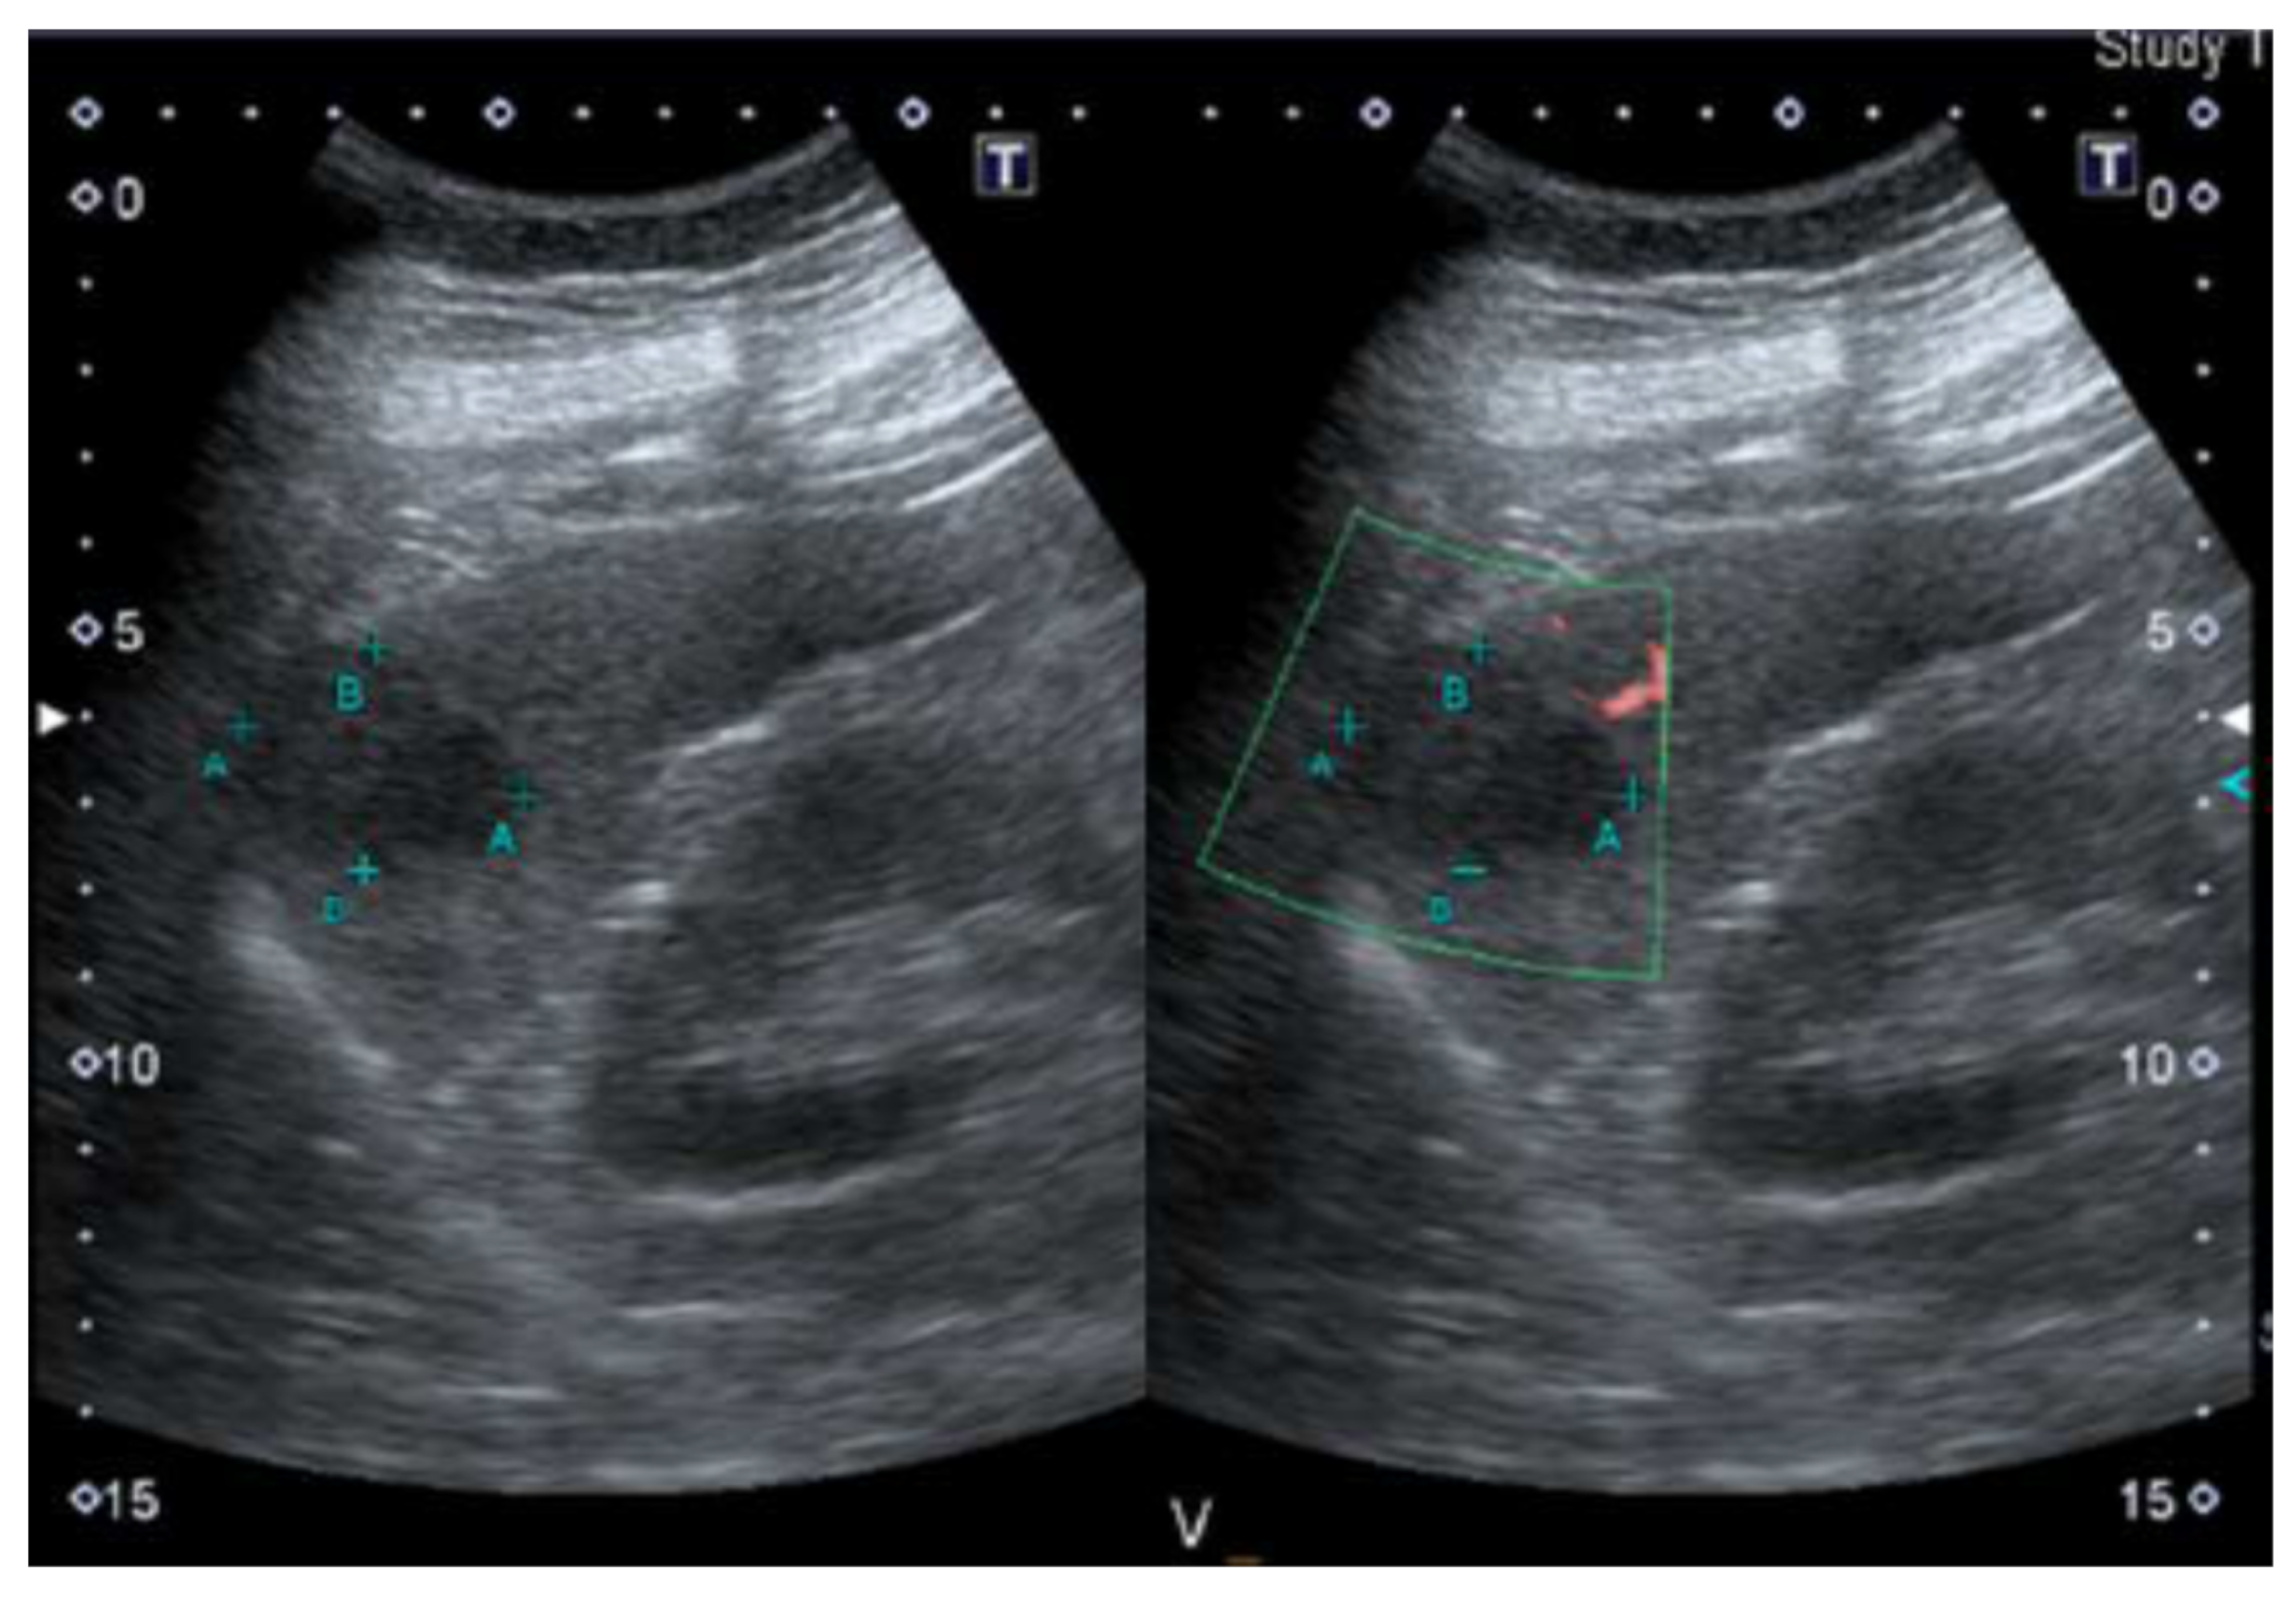

A 36-year-old man working as a nurse in our hospital presented with left upper quadrant (LUQ) pain, which had persisted for 1 week. He denied any past systemic disease, but the patient had undergone an abdominal ultrasound during a routine examination 4 months earlier, which had revealed a 3 cm hypoechoic splenic nodule (Figure 1). At that time, the treating physician had suggested a follow-up examination 6 months later.

Figure 1.

Abdominal ultrasound revealed a 3 cm hypoechoic splenic nodule during a routine examination 4 months earlier.